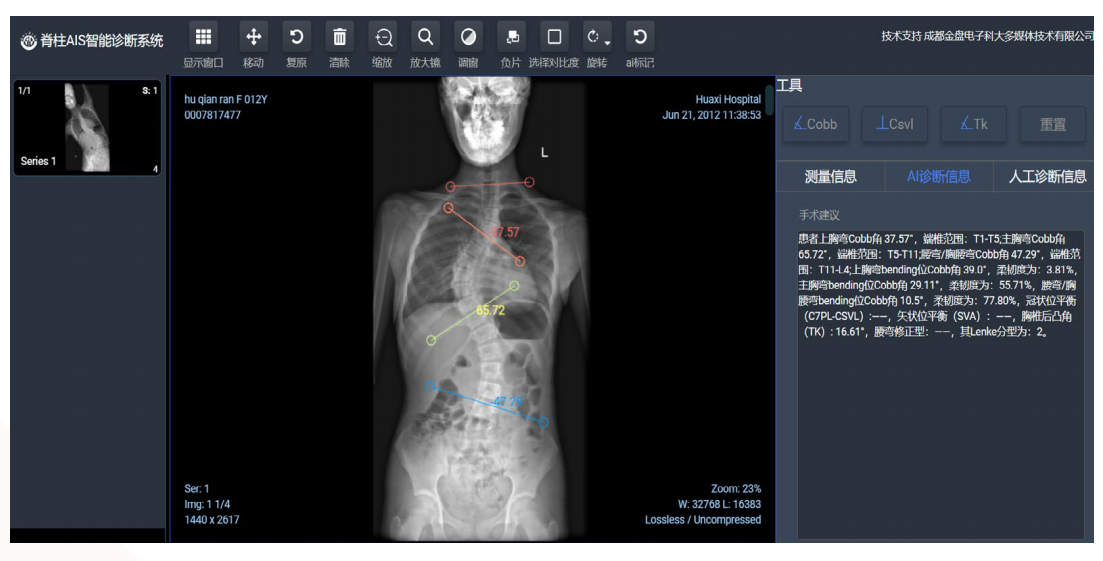

1.完善的测量系统:符合临床X光脊柱全长片阅片流程的AI测量系统。

2.高效率:产品读片+测量+诊断一共是3-5秒/病人,比医生的15分钟读片时间提速300倍。

3.高稳定:大样本测试下,cobb角测量误差与医生相当(5度以内)。